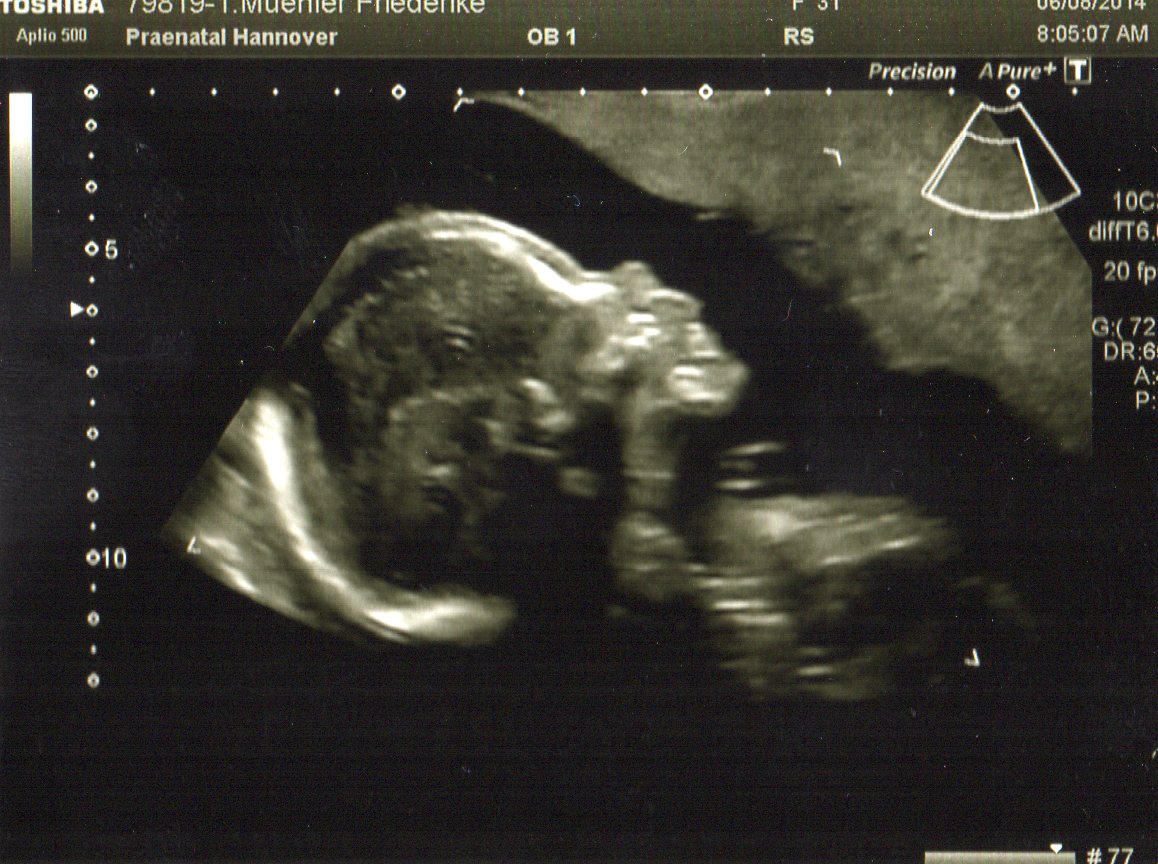

Heute gab es ein Fotoshooting der besonderen Art beim Opa auf Arbeit. Sein Kollege, der stellvertretende Chefarzt der Kinderklinik und gleichzeitig Guru des Ultraschalls, hatte sich bereit erklärt den werdenden Eltern noch ein paar aktuelle Fotos zu machen. Leider gab es kein 3D, aber dafür ein paar süße Fotos und vor allem Videos unseres Sohnemannes, der sich die ganze Zeit über ruhig verhielt und sich der Kamera, äh dem Schallkopf stellte.